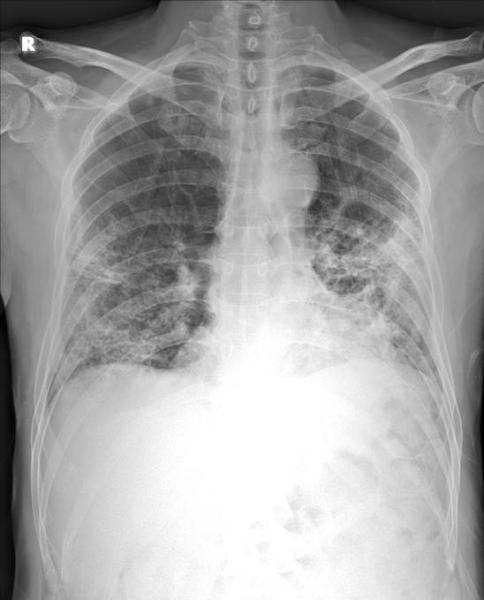

ITN has created a photo gallery designed to show the global impact of the novel coronavirus (COVID-19, SARS-CoV-2) in healthcare, and the world. The images are from ITN staff members, submitted from readers on Facebook, and shared from press releases, hospitals and government public relations sources. This page will be updated regularly with new photos.